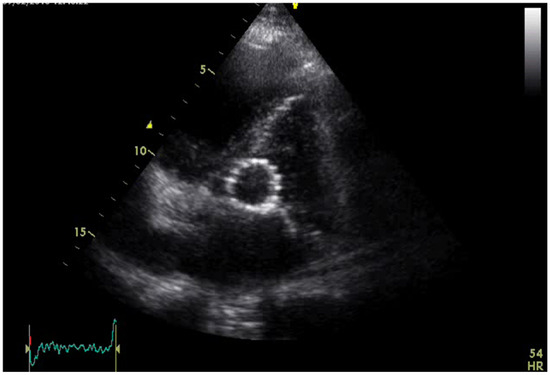

2. Case Presentation

3.8. Our Case